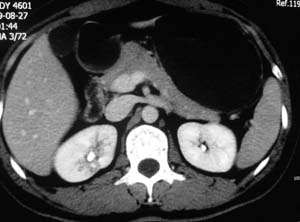

以下是引用子期在2010-3-19 20:47:00的发言:[br]血管畸形的ct增强应该有明显强化,本例并不相符合。本例双肾局部的略低密度影,累及肾盂,局部皮质明显变薄、内陷,增强扫描有轻度的强化,应考虑为炎性病变,患者为年轻男性,累及双肾的感染以结核较常见,可以没有明显的临床症状,尿中有时候也并不能查出什么;肾脓肿常有明显感染中毒症状,本例不符,另外一般的肾盂肾炎或肾小球肾炎通过小便就可确诊,其它还不能排除的是黄色肉芽肿性肾盂肾炎,然而单凭ct一般也很难鉴别。